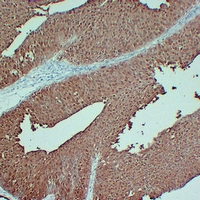

Immunohistochemical analysis of S100-P staining in human pancreatic carcinoma formalin fixed paraffin embedded tissue section. The section was pre-treated using heat mediated antigen retrieval with sodium citrate buffer (pH 6.0). The section was then incubated with the antibody at room temperature and detected using an HRP conjugated compact polymer system. DAB was used as the chromogen. The section was then counterstained with haematoxylin and mounted with DPX. -

Immunohistochemical analysis of S100-P staining in human transitional cell carcinoma formalin fixed paraffin embedded tissue section. The section was pre-treated using heat mediated antigen retrieval with sodium citrate buffer (pH 6.0). The section was then incubated with the antibody at room temperature and detected using an HRP conjugated compact polymer system. DAB was used as the chromogen. The section was then counterstained with haematoxylin and mounted with DPX.